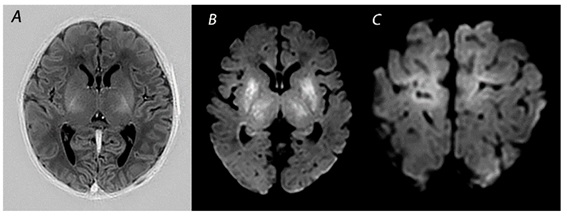

Brain MRI of a neonate with Neonatal HIE |

Neonatal hypoxic-ischemic encephalopathy (HIE) (Greece)

Clinical Area: Neurology

A term newborn was born at 38 weeks of gestational age, with a birth weight of 3500 g, delivered by caesarean section due to profound fetal bradycardia, to a 33-year-old woman. The mother had adequate prenatal care during pregnancy and an unremarkable past medical history.

The infant didn't cry im ...